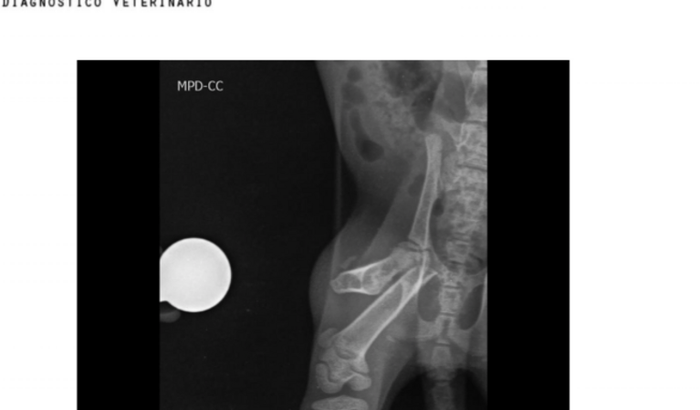

Eu sou a Liliane, preciso arrecadar  2.500,00 para cirurgia de uma gatinha que recolhi da rua e esta com o fêmur fraturado, se não fizer a cirurgia ness  momento mais tarde vai precisar amputar o membro. ver tudo

Eu sou a Liliane, preciso arrecadar  2.500,00 para cirurgia de uma gatinha que recolhi da rua e esta com o fêmur fraturado, se não fizer a cirurgia ness  momento mais tarde vai precisar amputar o membro.